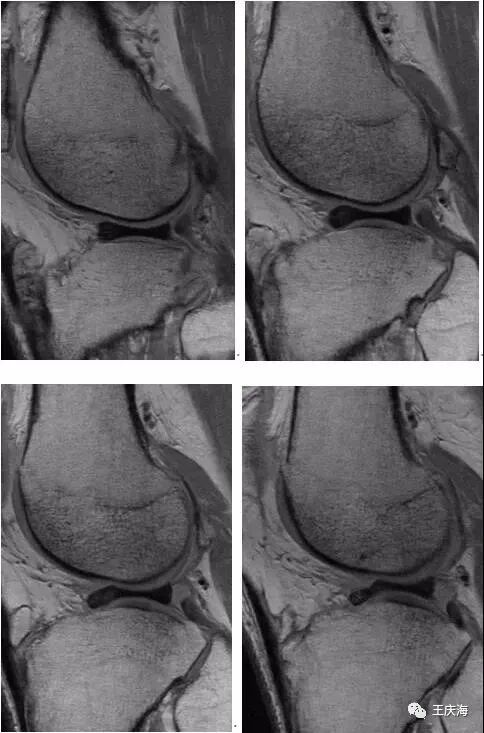

少见病例-内侧盘状半月板关节腔造影前(图A)后(图B)冠状面T1WI均呈现楔型盘状半月板,其体部宽度明显超过内侧平台关节面宽度的1/2以上。